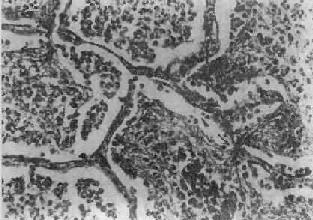

图9-15 大叶性肺炎 肺泡腔内充满纤维素性渗出物,纤维素丝穿过肺泡间孔,使相邻肺泡内的纤维素网互相连接

(一)细菌性肺炎 1.大叶性肺炎 大叶性肺炎(lobar pneumonia)主要是由肺炎链球菌感染引起,病变起始于肺泡,并迅速扩展至整个或多个大叶的肺的纤维素性炎。多见于青壮年,临床表现为骤然起病、寒战高烧、胸痛、咳嗽、吐铁锈色痰、呼吸困难,并有肺实变体征及白细胞增高等。大约经5~10天,体温下降,症状消退。 病因和发病机制 95%以上的大叶性肺炎由肺炎链球菌引起,尤以Ⅲ型者毒力最强。此外,肺炎杆菌、金黄色葡萄球菌、溶血性链球菌、流感嗜血杆菌也可引起。受寒、疲劳、醉酒、感冒、麻醉、糖尿病、肝、肾疾病等均可为肺炎的诱因。此时,呼吸道的防御功能被削弱,机体抵抗力降低,易发生细菌感染。细菌侵入肺泡后在其中繁殖,特别是形成的浆液性渗出物又有利于细菌繁殖,并使细菌通过肺泡间孔或呼吸细支气管迅速向邻近肺组织蔓延,从而波及整个大叶,在大叶之间的蔓延则系带菌渗出液经叶支气管播散所致。 病理变化 病变一般发生在单侧肺,多见于左肺下叶,也可同时或先后发生于两个以上肺叶。病变基本特征是肺的微循环障碍。由于毛细血管通透性增高,大量纤维蛋白原渗出于肺泡,使肺组织大面积广泛实变。病变早期,肺叶充血、水肿,肺泡腔内有大量浆液性渗出物,混有少数红细胞、中性粒细胞和巨噬细胞,并含有大量细菌。1~2天后,即有大量纤维蛋白原渗出,肺泡腔内充满混有红细胞、中性粒细胞、巨噬细胞的纤维素性渗出物,纤维素丝可穿过肺泡间孔与相邻肺泡中的纤维素网相连(图9-15)。病变肺叶质实如肝,明显肿胀,重量增加,呈灰白色(图9-16)。如血管损伤较重、出血较多,外观可呈红色。大约经5~10天,炎症消退,细菌被吞噬细胞吞噬清除,渗出物被溶解,或经淋巴管吸收或被咳出。大叶性肺炎时,肺组织常无坏死,肺泡壁结构也未遭破坏,愈复后,肺组织可完全恢复其正常结构和功能。